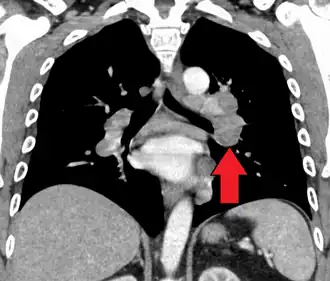

Hilar adenopathy especially on the person's left (AP CXR) -

Hilar adenopathy especially on the person's left (lateral CXR) -

Hilar adenopathy especially on the person's left (coronal CT) -

Hilar adenopathy especially on the person's left (transverse CT)